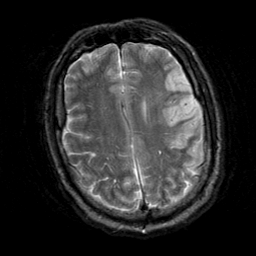

Subacute Stroke, overlay -- Slice #18

[Home][Help][Clinical] Slice 18